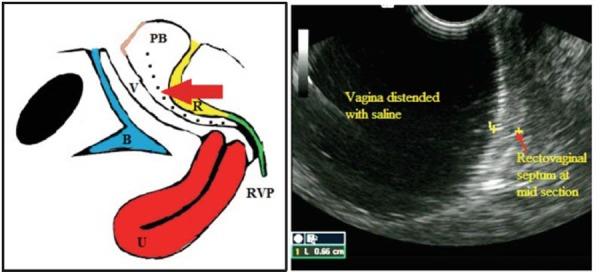

: The aim of this study was to perform saline sonovaginography (SVG) in women with suspected rectovaginal endometriosis (RVE) in order to establish the thickness of the rectovaginal septum (RVS) in this population and to predict the presence or absence of RVE. : Prospective observational pilot study. Women undergoing laparoscopy for possible endometriosis on the basis of history or clinical examination were offered to participate in the study. All women underwent saline SVG during general anesthesia just prior to their laparoscopy. RVS nodules were visualised as hypoechoic lesions of various shapes. The sonologist predicted whether or not a nodule was present in the retrocervical area or in the RVS. The thickness of the posterior vaginal wall ± RVS was then taken at three points in the mid-sagittal plane: at the posterior fornix (retrocervical area), at the middle third of the vagina (upper RVS) and just above the perineal body (lower RVS). The diagnosis of RVE was established using the gold standards of laparoscopy and histological confirmation. The RVS thickness was then compared between women with RVE and the absence of RVE. : Twenty-three women were enrolled in the study. Mean age was 38 years (33-44 years). A history of endometriosis was present in 72.7% (8/11). RVE was confirmed in 17.4% (4/23). Visualisation of a hypoechoic nodule at saline SVG demonstrated sensitivity and specificity of 75% and 95%, respectively. All rectovaginal nodules were located in the retrocervical region. Mean diameter (SD) of RVE nodules was 27.3 (± 9.4) mm. Mean thickness of vaginal wall ± RVS at the posterior fornix, at the middle third of the vagina and just above the perineal body was 5.1, 1.4 and 4.0 mm, respectively. These measurements were not significantly different in the presence of a rectovaginal nodule. : Using saline SVG, we have established the mean RVS thickness in a small group of women with suspected RVE. Although the numbers are small, there was no correlation between RVS thickness and presence of RVE. The visualisation of hypoechoic lesions at saline SVG seems to be the best ultrasonographic predictor for RVE. SVG is a valuable pre-operative tool for the assessment of RVS and for the prediction of RVE, which allows for the mapping and planning of advanced endometriosis surgery.